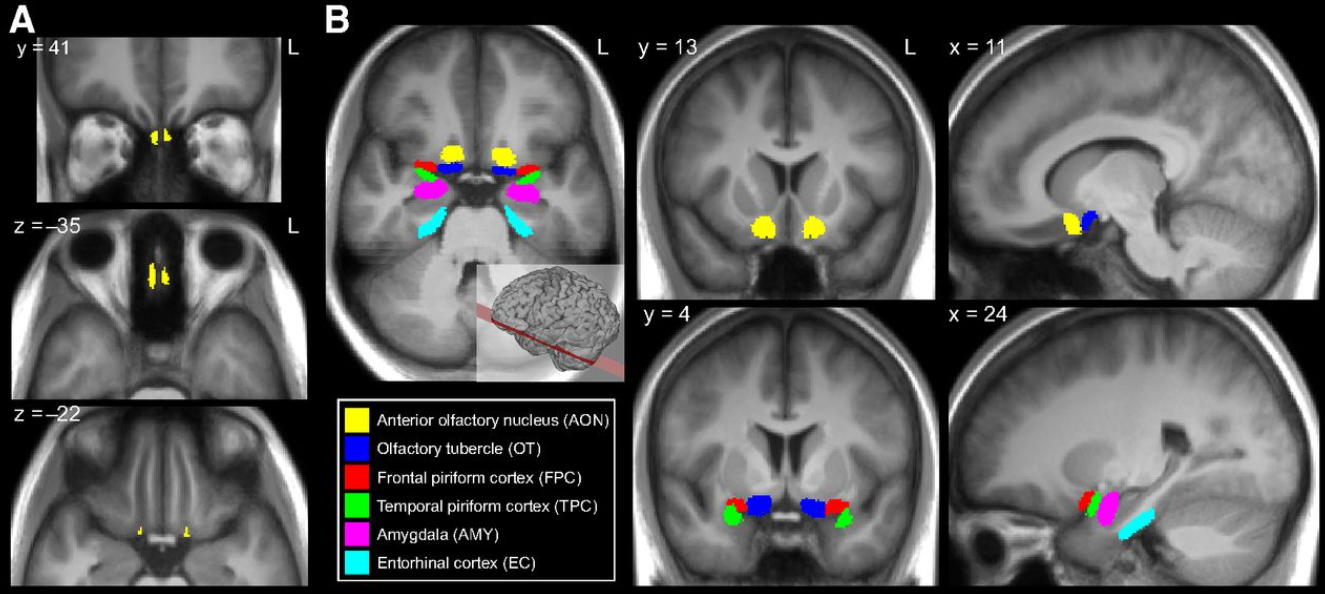

Как мозг идентифицирует разные запахи: обонятельная кора – первичное восприятие запаха

Обонятельная луковица, собирает в себя сигналы от разных рецепторов и напрямую передаёт их в первичную обонятельную кору, в обход таламуса, что уникально для сенсорных систем.

Здесь формируется основное распознавание запаха как отдельного «образца/шаблона»: «запах розы», «горелый запах», «тухлятина» и т.п. Это первая стадия, где активность разных наборов возбужденных полей нейронов превращается в осознанное восприятие запаха.

Лимбическая система (миндалевидное тело) – эмоциональная окраска запахов

Обонятельные сигналы напрямую идут в миндалевидное тело — центр тревоги, страха и других эмоциональных реакций. Это добавляет запахам мощную эмоциональную компоненту, чего нет у других чувств.

Гиппокамп – связь обоняния с памятью

Гиппокамп участвует в долговременном запоминании и ассоциациях. Обонятельные сигналы туда идут напрямую, формируя сильную связь между запахом и воспоминанием.

Орбитофронтальная кора – сознательное распознавание и оценка запахов

После обработки в обонятельной коре сигналы передаются в орбитофронтальную кору головного мозга. Здесь происходит:

Осознанное восприятие запаха – «это кофе», «это лимон», «это море».

Оценка запаха – приятен он или неприятен.

Выбор реакции на запах – понюхать или отойти в сторону от источника.